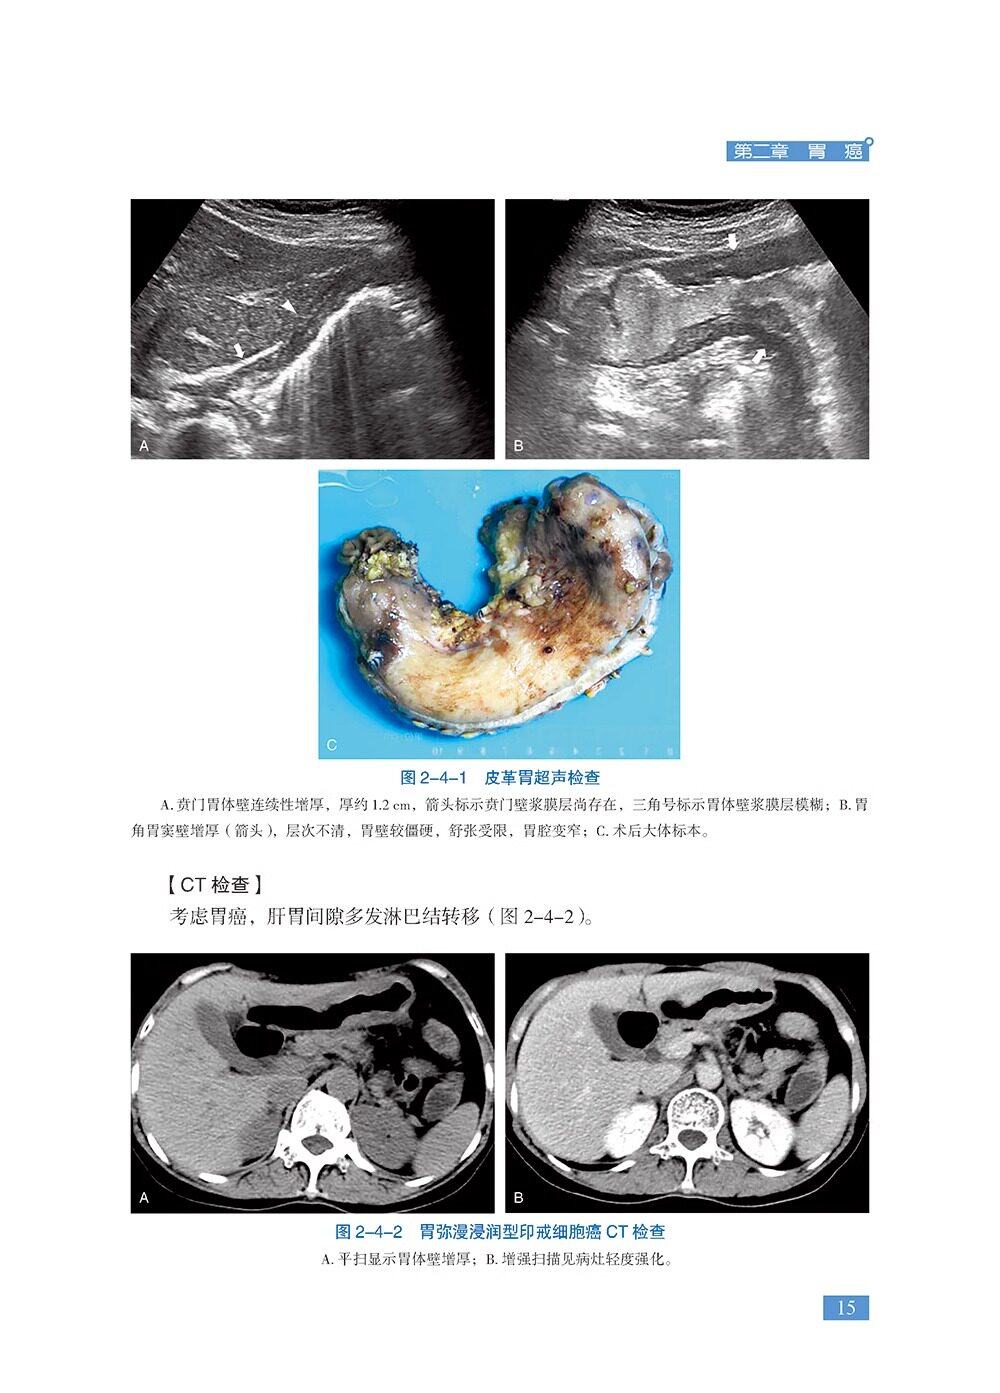

本书是《胃肠疾病超声诊断学》的姊妹篇,共18章,精心挑选了120个胃肠超声经典病例、疑难病例、罕见病例及误诊病例。涵盖各种胃肠道肿瘤、消化性溃疡、炎症性肠病、急腹症、先天异常、胃肠周围血管疾病等内容。每个病例从病史、体格检查、实验室检查、超声检查、其他影像检查、诊疗经过、病理诊断等方面进行详细阐述,并针对病例的超声特征及误诊原因等进行精准解析。全书精选了700余幅超声、CT、MRI、病理等图片,内容丰富、图文并茂,具有很强的实用性和指导性。适合各级超声医师及相关学科临床医师、医学院校师生阅读。